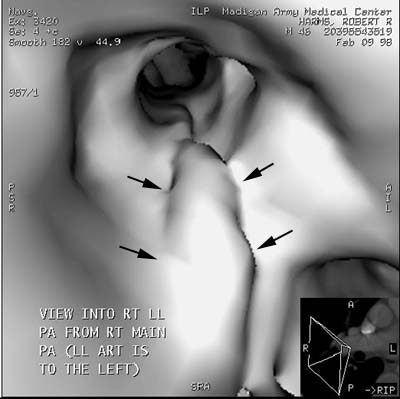

Endolumenal shaded surface images can also be performed: